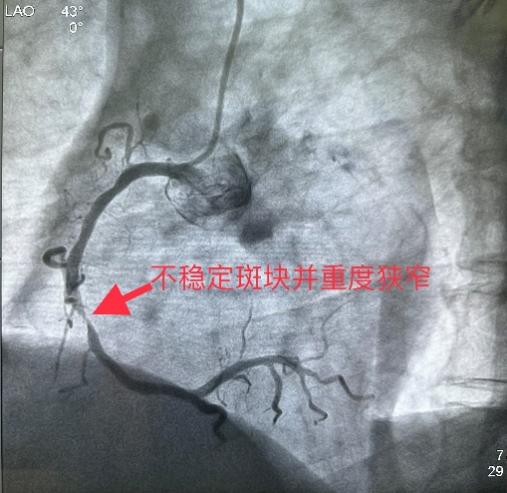

5月31日经过充分的术前准备,雷新军教授带领景林德博士和李瑞峰医生按照预定方案为患者实施了手术。冠脉造影示:RCA 2段节段性狭窄约25%,末端狭窄约90%,为不稳定斑块,血流TIMI 3级(图2a)。决定干预右冠:6F SAL1.0指引导管到位后,先操控Sion导丝通过病变至LV末端,然后再沿导丝送入血管内超声(intravenous ultrasound,IVUS)检查,结果显示RCA 2段末狭窄最重部位血管面积为2.30 mm2,斑块负荷为85%,手术指征明确(图2b)。首先,使用NC Balloon 3.0 x 15 mm 20 atm预扩张靶病变,造影示残余狭窄约25%,再在IVUS指导下植入Xinsorb BRS 3.5 x 28 mm,随后采用NC Balloon 3.5 x 9 mm 16atm逐段后扩张,造影显示支架充分膨胀,血流TIMI 3级(图2c-g)。最后,进一步使用IVUS评估手术情况,结果显示:支架充分膨胀,贴壁良好,支架远近端未见夹层,血管面积为8.01 mm2,手术效果非常满意(图2h)。术中患者无特殊不适,术后病人安返病房。

图2 经皮冠脉介入治疗